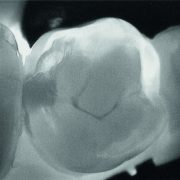

KaVo DIAGNOcam je najnaprednejša naprava za odkrivanje kariesa, ki temelji na DIFOTI tehnologiji (digital imaging fiber optic transillumination) s presvetlitvijo zoba. Pomaga odkrivati skrite kariozne lezije in razpoke v zobeh in to brez uporabe rtg sevanja.

KaVo DIAGNOcam je najnaprednejša naprava za odkrivanje kariesa, ki temelji na DIFOTI tehnologiji (digital imaging fiber optic transillumination) s presvetlitvijo zoba. Pomaga odkrivati skrite kariozne lezije in razpoke v zobeh in to brez uporabe rtg sevanja. Tako je še posebej primeren za otroke, paciente z rakavimi obolenji, ortodontske paciente in nosečnice!

Ko pomislite na karies, avtomatično pomislite na vrtanje? To je sedaj lahko preteklost. Če se karies odkrije dovolj zgodaj, se lahko s pomočjo pravilne higiene, uporabe fluoridovih premazov in pravilne prehrane zob remineralizira in karies izgine. V primeru, da pa je vseeno potrebna plombica, pa je le-ta zelo majhna in je vrtanje praktično neboleče.Zob Cam

V povprečju zobozdravnik s prostim očesom odkrije 70% kariesa. S pomočjo RTG diagnostike se ta odstotek bistveno zviša, okrog 90%. Če pa k temu dodamo še DIAGNOcam pa lahko tako odkrijemo skoraj vse kariese.

Tako je KaVo DIAGNOcam NEPOGREŠLJIV PRIPOMOČEK V SODOBNEM ZOBOZDRAVSTVU.